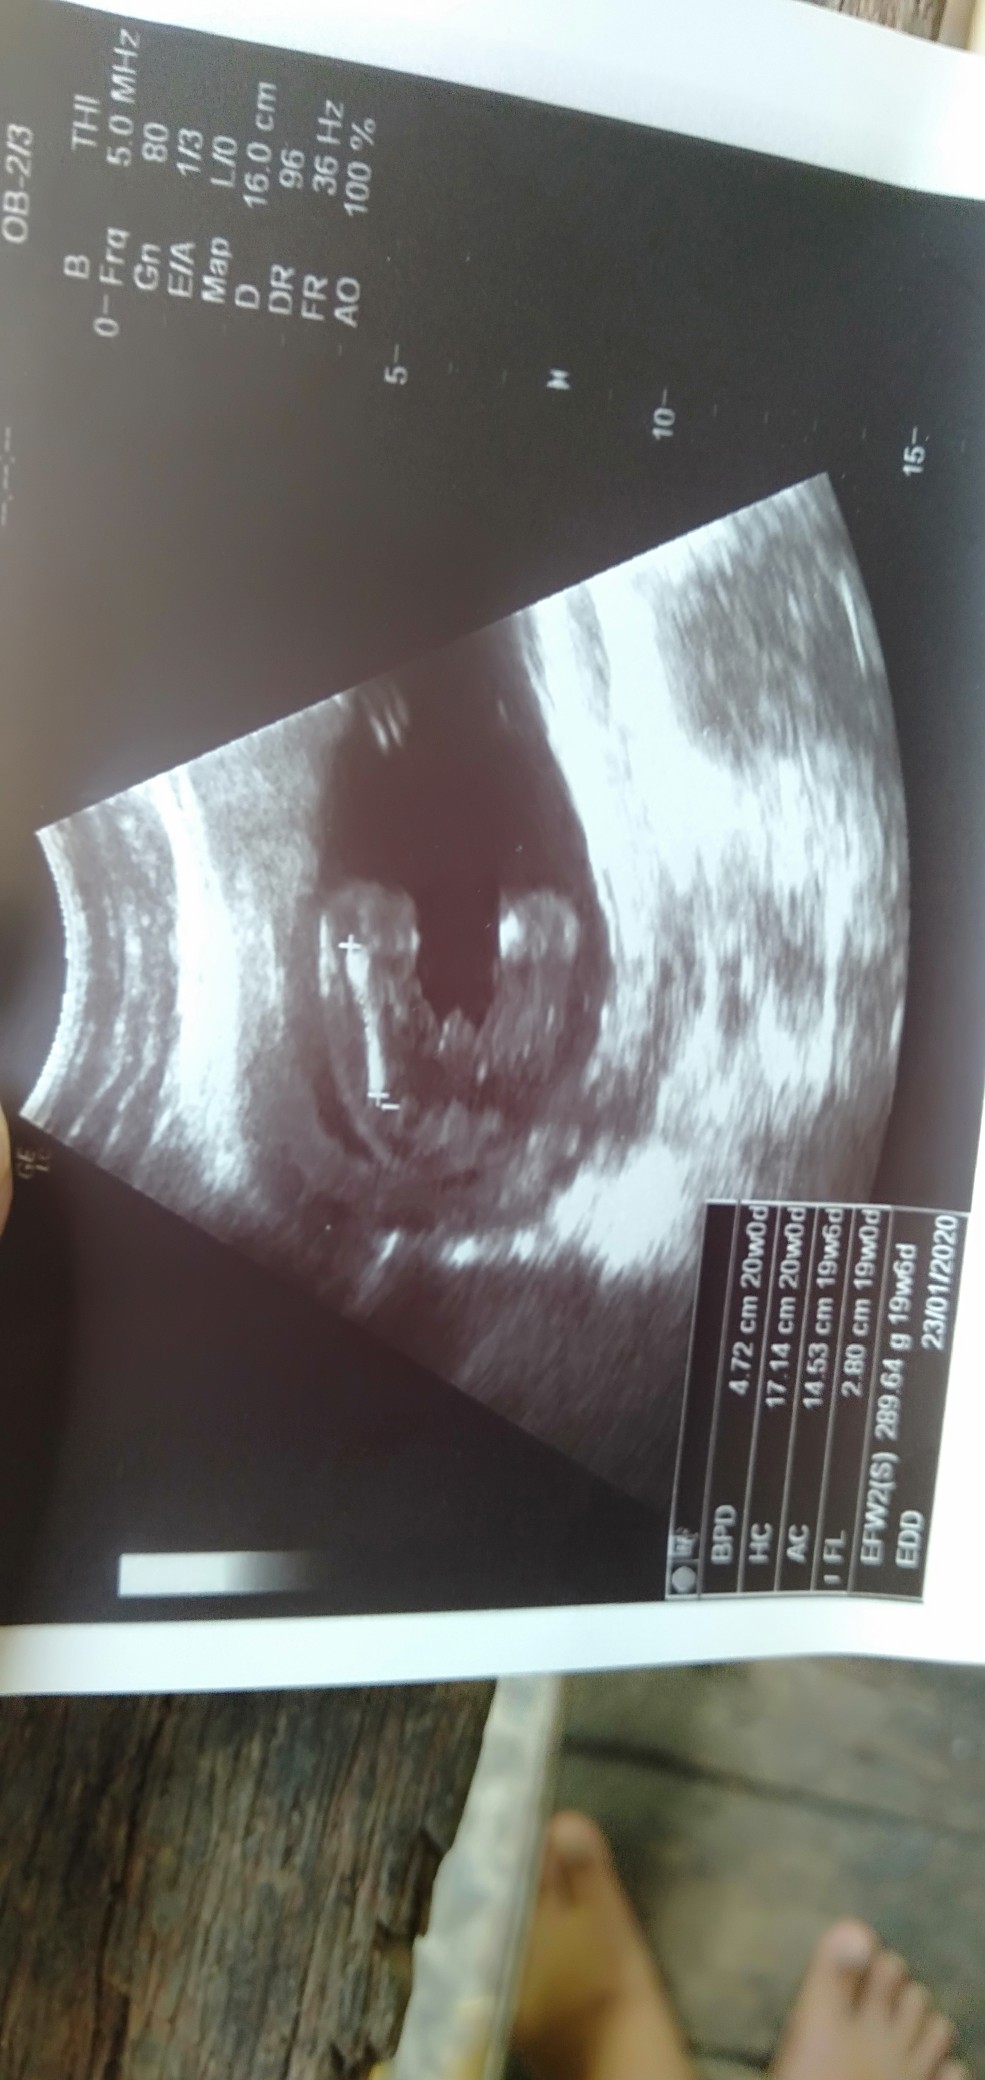

เพศอะไรคะแม่ๆ

แม่ๆช่วยดูหน่อยค่า เพศอะไรเอ่ย

ชายรึป่าวค่ะ

ชายค่ะชัดเจน

ผู้ชายแน่นอน

เพศชายแน่ๆ 100%

จู๋มาเชียว🤭

ผช แน่นอนค่ะ

น่าจะผช.นะคะ

ผู้ชายค่าา🥰

ชายจ้าาา 😁😁